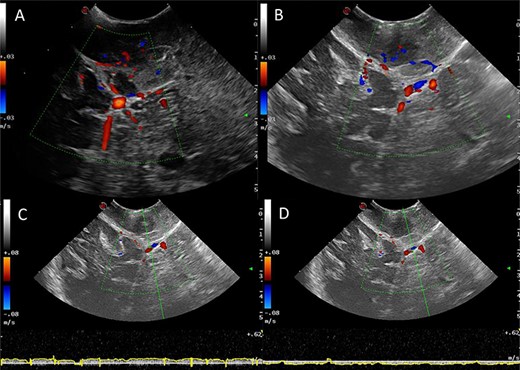

Power and colour Doppler were used throughout to obtain real-time information about the location and function of dural venous sinuses. Blood flow was preserved in the sinuses and, as we debulked the tumour, we were able to demonstrate bi-directional flow within the sinuses (Fig. 3). This suggested resolution of venous obstruction and indicated the dural venous sinuses had regained their functionality. Medially tumour was found invading the torcula and right transverse sinus, and a decision was made to leave the residual tumour and to preserve the sinuses (Fig. 4). We achieved a Simpson Grade 4 resection without any intraoperative complications.

Intraoperative images at the end of resection; Duplex US images (2D image with overlay of colour Doppler) of the initial appearances of the straight sinus (A) and appearance at the end of resection (B); a bidirectional flow in the straight sinus is apparent after tumour resection, this was not present prior to tumour debulking; the Triplex Doppler confirms the bidirectional flow in the straight sinus (C and D).